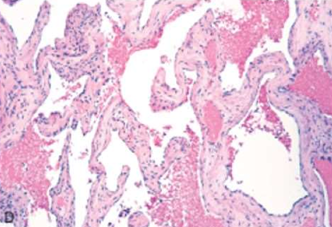

Vascular neoplasm: Malignant

Angiosarcoma

.Malignant endothelial cells forming irregular, anastomosing vascular channels.

.Atypia, mitotic activity, and multilayering of endothelial cells.